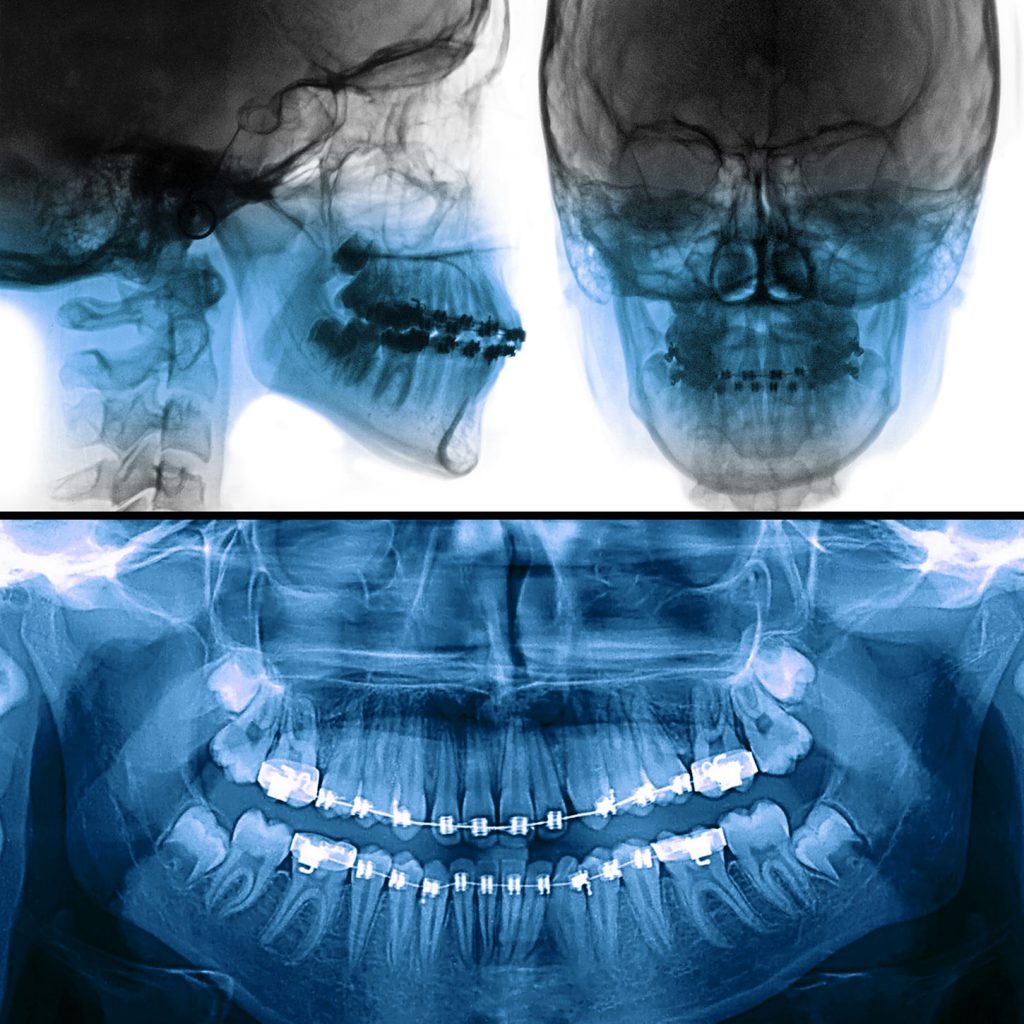

Digital X-Rays

Digital radiography is a form of radiography that uses x-ray–sensitive plates to directly capture data during the patient examination, immediately transferring it to a computer system without the use of an intermediate cassette.